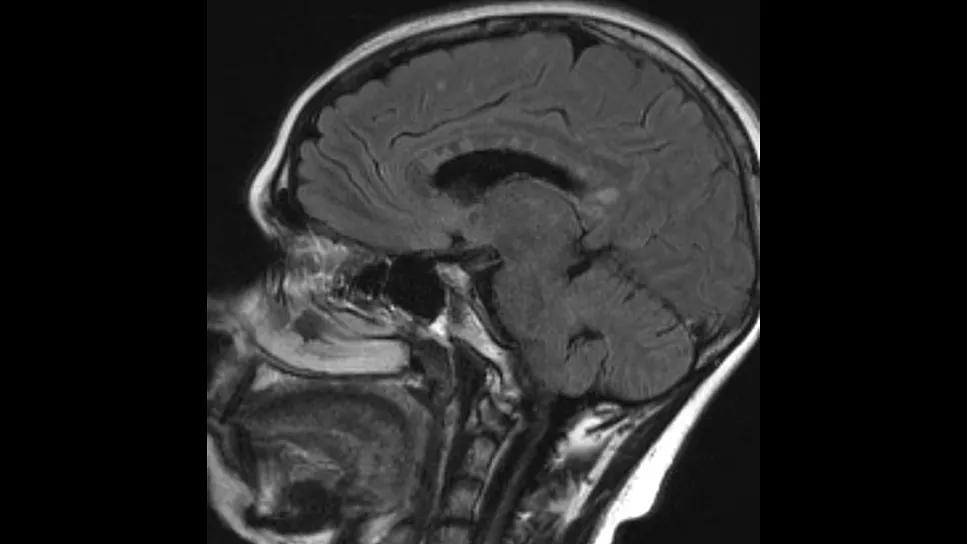

MRI scan of the side of a human head

Cerebrovascular involvement and deep brain lesions are prominent and underrecognized MRI features of Susac syndrome (SuS) and correlate with vision and hearing loss in those affected.

SuS involves the central nervous system (CNS), retina and cochlea. Clinical symptoms include unilateral or bilateral visual field defects, sensorineural hearing loss, headache, confusion and memory impairment. The hallmark cerebrovascular findings on brain MRI in patients with SuS include corpus collosum lesions that resemble snowballs, but imaging can also show small-vessel infarcts in other areas of the brain similar to the small-vessel subtype of PACNS.

MRIs were available for 57 patients, of which 48 (84%) revealed corpus callosum lesions. Cerebellar, brainstem and middle cerebellar peduncle involvement was seen in 47.4%, 24.6% and 15.8% of the scans, respectively. Deep gray matter lesions were noted on 35.1% of MRIs and leptomeningeal enhancement on 19.3%. Over half the scans (52.6%) showed small-vessel infarcts, nearly all of which (96.7%) were deep subcortical.